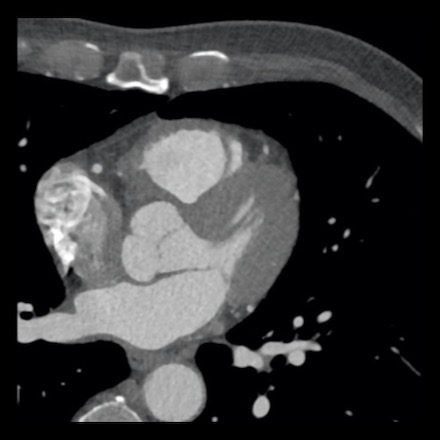

case 4 – CAD-RADS 3/P1/I+ thrombus left ventricle

First, scroll through the CTA images.

How would you describe the findings on the coronary CTA?

The findings are:

- Moderate (50-69%)

stenosis in the proximal LAD caused by a non-calcified plaque. - Variant of

sinoatrial (SA) nodal artery. The artery usually arises from the RCA as a second

branch after the conus artery, however in this case it arises from the LCX,

courses behind the aorta, anastomosing with the right atrium and with a small

branch supplies the SA-node of the heart. - Thrombus in the

apex of the left ventricle. - CTP was performed

in this patient. CTP showed a perfusion defect at stress imaging in the

territory of the LAD (I+), at rest no perfusion defect was visible.

This patient classifies as CAD-RADS 3/P1/I+, which means

this patient requires further investigation.